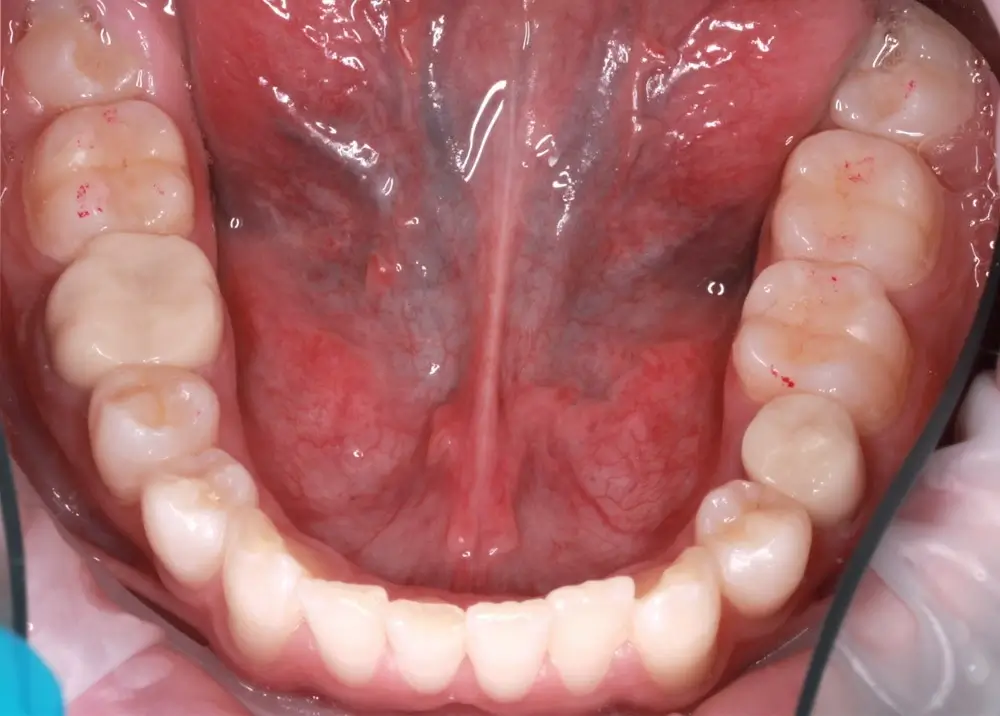

Кейс 9

Бирковская Екатерина Александровна

Количество кап ВЧ 23

Количество кап НЧ 23

ДО

ПОСЛЕ